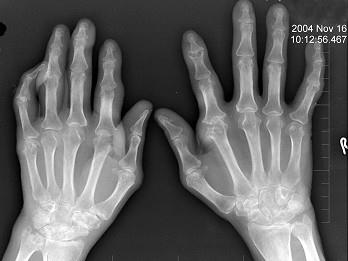

问题 男,72岁,手足小关节红肿热痛,白细胞升高,血沉快,血尿酸升高,结合图像,最可能诊断是?(?)

选项 A.类风湿关节炎 B.退行性骨关节病 C.痛风性关节炎 D.假痛风 E.滑膜炎

答案 C